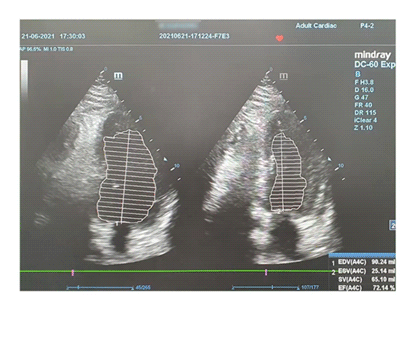

Ini hasil pemeriksaan echonya :

Tampak tanda panah pada bagian 1, 5 dan 6 yang semula mengalami kelemahan, berhasil menjadi normal kembali. Seluruh bagian jantung dapat berkontraksi dengan baik. Hal ini menandakan bahwa telah terjadi perbaikan mikrosirkulasi yang luar biasa pada seluruh bagian jantung.

Yang awalnya terdapat 3 segment dari 6 segment yang mengalami kelemahan.. kini seluruh 6 segment dapat berkontraksi dengan kuat.

Selain itu, pompa jantungnya juga mengalami kenaikan. Nilai Ejection Fractional yang semula 31,86 % naik menjadi 72,14% hanya dalam waktu 1 bulan